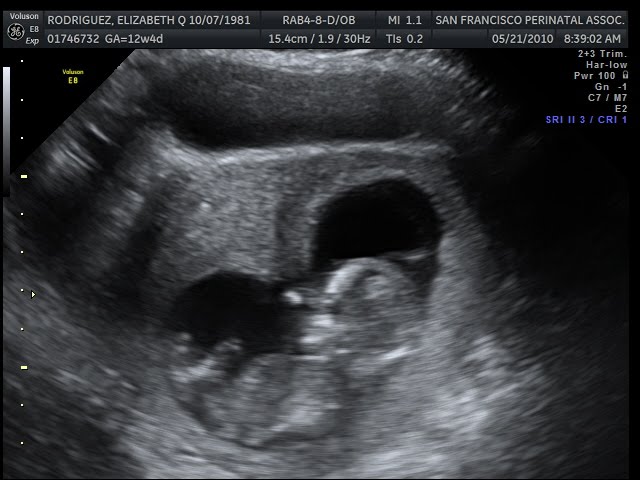

Back to the most important thing in the world, life! Today was my integrated screening, I've been waiting for this for sooo long!!!!! I popped out of bed at 5am, ready to go by 7am, and had to chillax by the time our appt came around at 8:30am, lol. Seeing our baby actually look like a baby was surreal! It was the first appointment where I didn't cry hysterically because I was taken aback by my baby's beautiful dancing/ballet, it was my first proud mommy moment! My husband and I tried to zone in on our baby's genitalia, but couldn't see a thing since baby's legs were crossed the majority of the time. I have a feeling it's a girl... either way I'm elated since the chance baby has down syndrome is 1 in 30,000, woohoo!!!

Alright, so more fun stuff- pics!!! I have to cut this blog short due to the fact that I have to finish packing the rest of the apartment and study some more for my final tomorrow ;)

Look at my beautiful baby sucking it's thumb :')

12w4d!!!